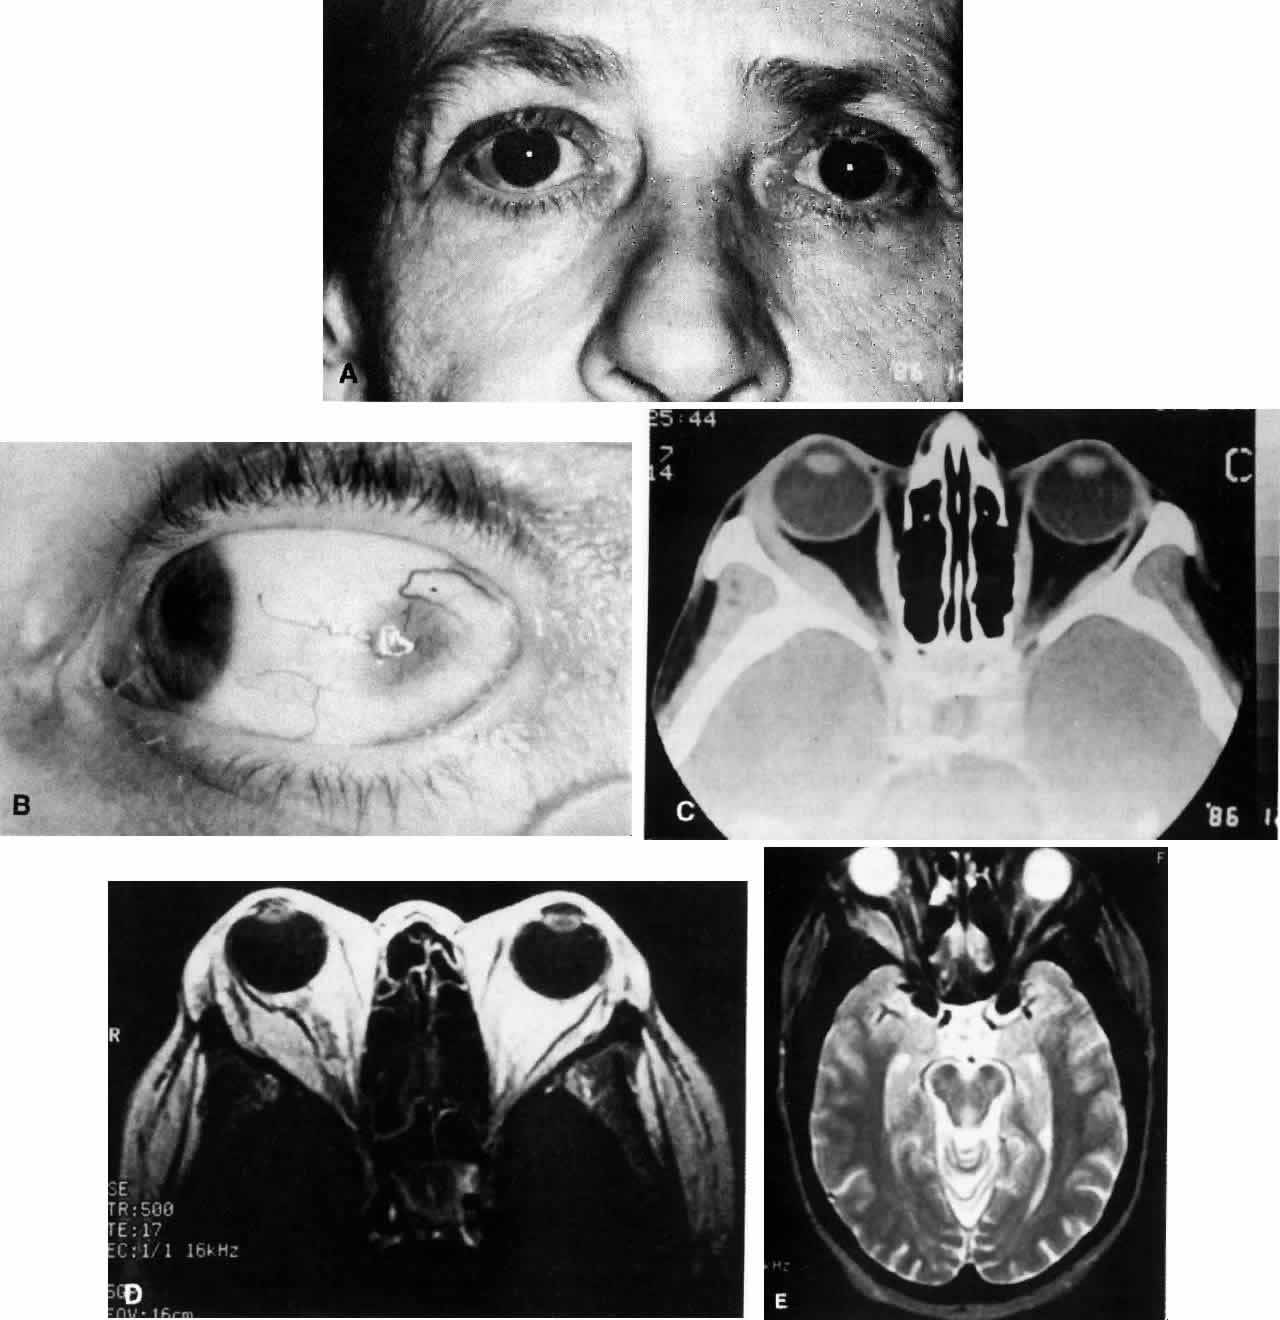

The manifestations of idiopathic orbital inflammation vary depending on which orbital structures are involved (Figs. 1 THROUGH 4).3–7 The most common features of this process are pain and proptosis. These symptoms develop rapidly, usually within hours to days, although in some cases they may develop over several weeks. In addition, generally there is chemosis and conjunctival injection often over the extraocular muscle insertions, as well as eyelid edema and ptosis. However, these findings are not always present and painless, quiet proptosis may occur. Proptosis may not be present in instances of dacryoadenitis.5,11 Instead, eyelid edema and a palpable painful mass in the lateral eyelid may be present. Diplopia and painful disturbances of ocular motility are usually present in the diffuse form of the disease, the superior orbital fissure syndrome, or in myositis but are less common in cases of localized “pseudotumor.” Visual loss is unusual but may be associated with intraocular inflammation as well as perineuritis of the optic nerve. Nonspecific constitutional symptoms of malaise and fatigue may also be associated with these various orbital symptoms.26

Fig. 1. A. A 36-year-old woman presented with right-sided pain and proptosis occurring over a several-day period. Externally the eye is quiet and does not appear inflamed. The patient had no complaints of diplopia or other visual disturbances. Tissue obtained at biopsy demonstrated idiopathic orbital inflammation. B. Axial CT image from the same patient demonstrates bilateral orbital masses located laterally in the orbits. Note that masses are ill defined and do not appear to have a capsule. The masses are molded to the bony orbital walls without evidence of any bony irregularities. C. Coronal CT image from the patient again shows the presence of bilateral orbital masses apparently involving the lateral rectus muscles.

Fig. 2. A 54-year-old woman presented with acute orbital inflammation demonstrating significant proptosis and inflammatory signs involving the right orbit. In addition to severe pain, the patient had diplopia secondary to orbital edema and inflammation.

Fig. 3. A. A 62-year-old woman presented with diplopia and minimal right-sided proptosis. B. Enlarged lateral rectus muscle is visible subconjunctivally. C. Axial CT image confirms myositis involving the lateral rectus muscle. Note that the muscle as well as its tendon are involved in the inflammatory process in contrast to muscle involvement in thyroid-related orbital disease. D. T1-weighted MRI image demonstrating myositis involving the lateral rectus muscle. In this case the muscle belly is enlarged but the tendon appears relatively unaffected. E. T2 weighted MRI image of orbital myositis showing little difference in appearance of muscle between T1- and T2-weighted images.